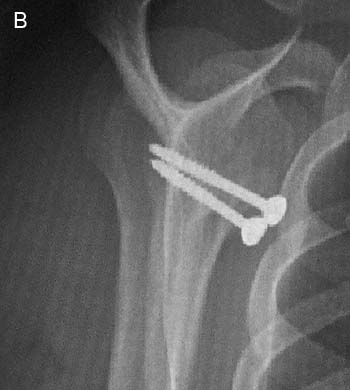

Figura 7: Radiografía anteroposterior de Hombro, se observa sutura de anclaje en defecto de Hill-Sach.

Figura 8: Radiografia anteroposterior, se observa alo injerto humeral fijado con 2 tornillos.